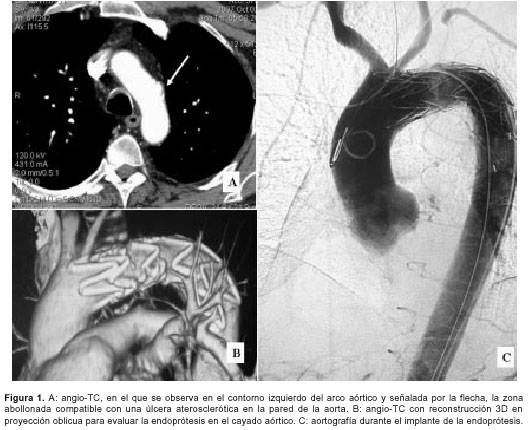

El síndrome aórtico agudo constituye un proceso agudo de la pared aórtica que debilita la capa media, condicionando un riesgo potencial de complicaciones graves. En la mayoría de los casos se debe a una disección de aorta (80%), pero existen otras dos entidades que con menor frecuencia lo condicionan, como el hematoma intramural (15%) y la úlcera aterosclerótica penetrada (5%) (1,2). Se presenta el caso de un varón de 49 años, fumador, hipertenso y dislipémico no controlado farmacológicamente, que acude al servicio de urgencias refiriendo un dolor en el centro del tórax de inicio súbito, intenso y no irradiado, de tres horas de evolución. No presentaba compromiso hemodinámico y el dolor no se aliviaba con nitroglicerina ni morfina. Los electrocardiogramas seriados, la radiografía de tórax, así como las enzimas cardiacas, no mostraron alteración alguna. Ante la sospecha clínica de un síndrome aórtico agudo. se realizó un angio-TC (figura 1A) que evidenció en el contorno izquierdo del cayado aórtico, medio centímetro después de la salida de la arteria subclavia izquierda, una formación sacular abollonada, sobre una zona de calcificaciones parietales, compatible con una úlcera aórtica aterosclerótica.

La úlcera aterosclerótica penetrada aguda y sintomática tiene un riesgo igual o superior a la disección clásica, sobre todo las localizadas en aorta ascendente (3), por lo que se aconseja un tratamiento invasivo, ya sea quirúrgico o basado en el implante por cateterismo de prótesis endoluminales (4). Integrando el cuadro clínico con el hallazgo de la tomografía, ante el riesgo potencial de complicaciones graves y lo impredecible de la evolución, se implantó por vía femoral una endoprótesis autoexpandible Relay de 30 mm x 100 mm con buen resultado (figuras 1B y 1C).